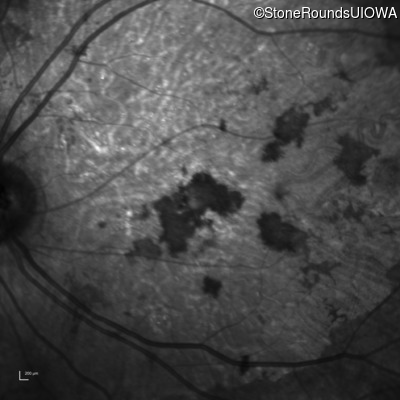

Infrared Fundus Photograph - Left - 20/300 sc

Exemplar